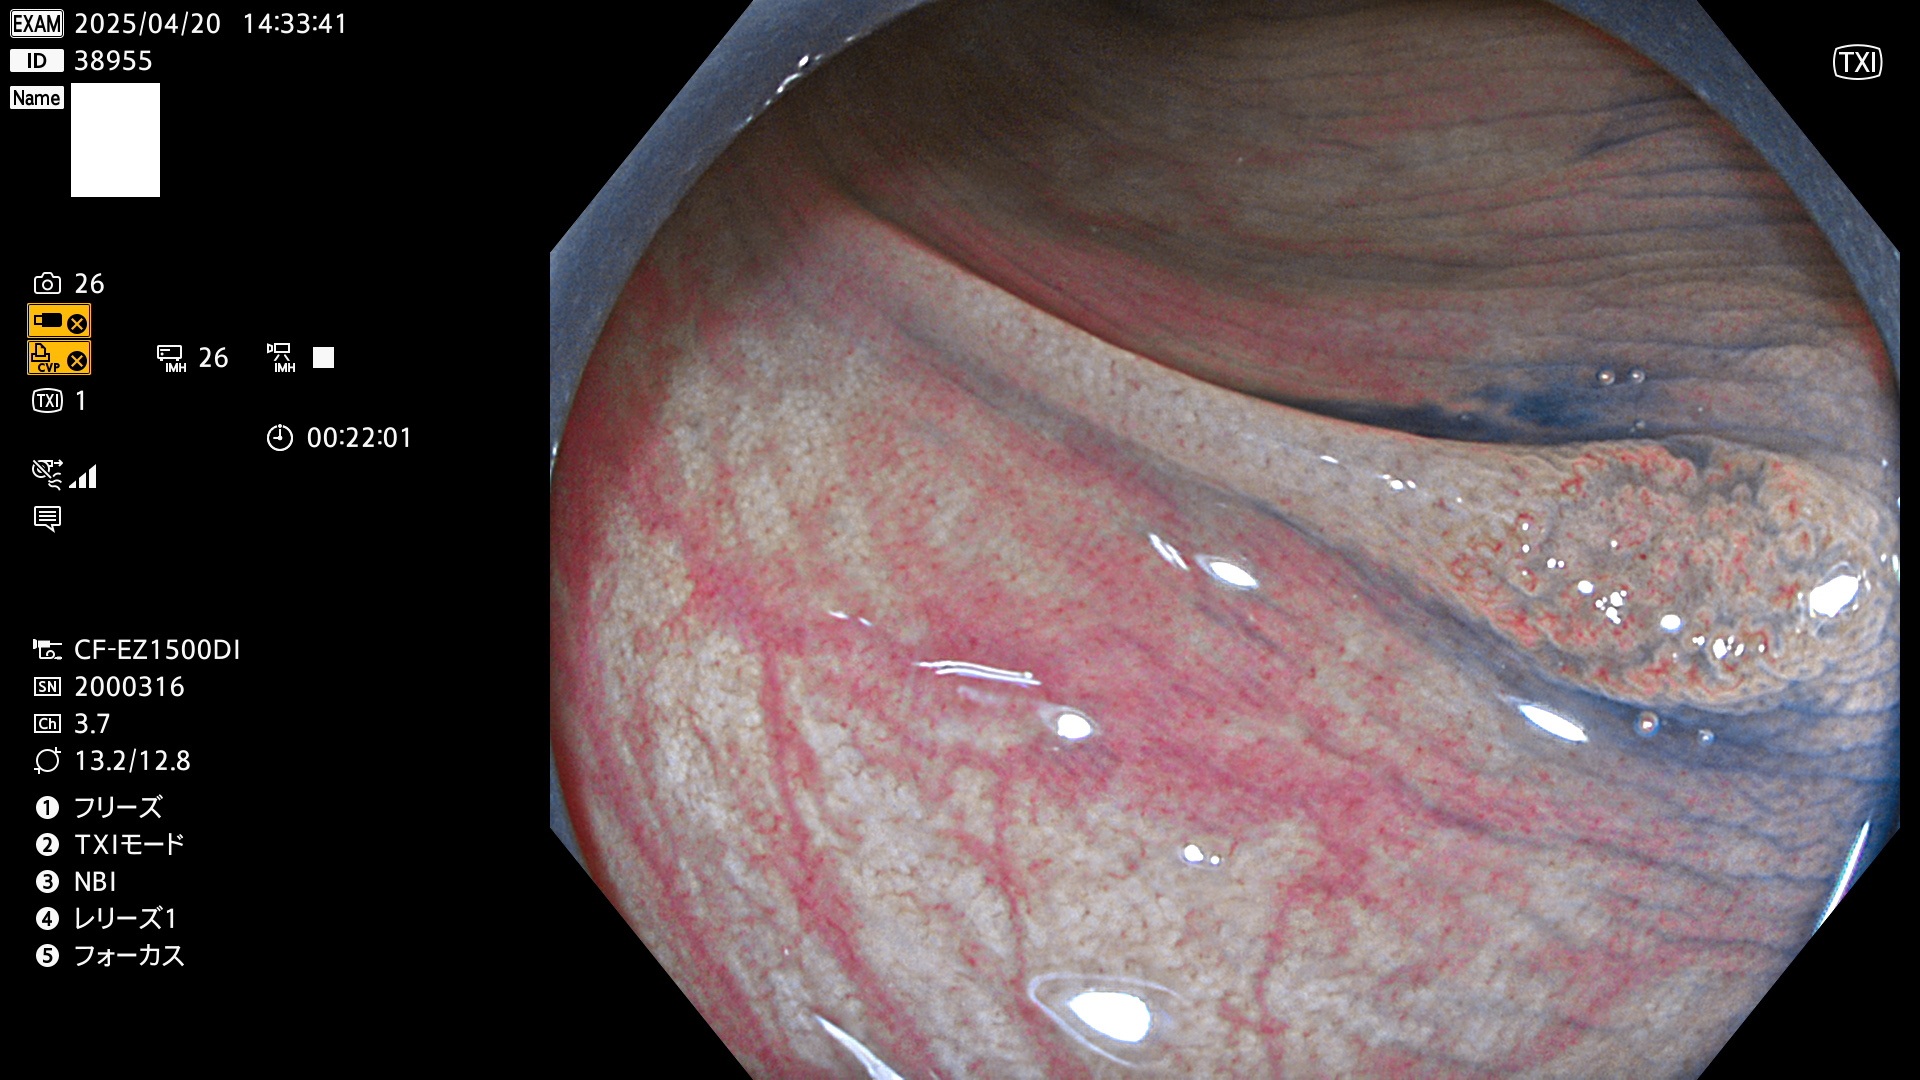

今週のUb、Uc型腺腫

完全に平坦な物をUb、陥凹している物をUcと呼びます。Ubは認識が困難で、Ucはびらん(炎症)と紛らわしいために見落とされやすく、「内視鏡後・大腸癌」の原因になります。

毎週の検査(木・金・土・日)に発見されたUb、Uc型・腺腫を、その週の日曜の夜にUPし1週間、提示します。

抽出の対象期間 2025年4月17日〜4月20日の4日間(48件の検査)8個 (8/48=16%)